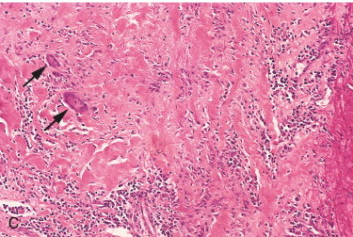

What are the histological findings of Takayasu’s Arteritis?

histology is the same as temporal arteritis

giant cells are present

inflammation across all 3 layers of artery

acute phase - transmural inflammation and fibrinoid necrosis

chronic phase - fibrous wall thickening

stages can coexist!

very cellular, inflammatory thrombus with relative vessel wall sparing